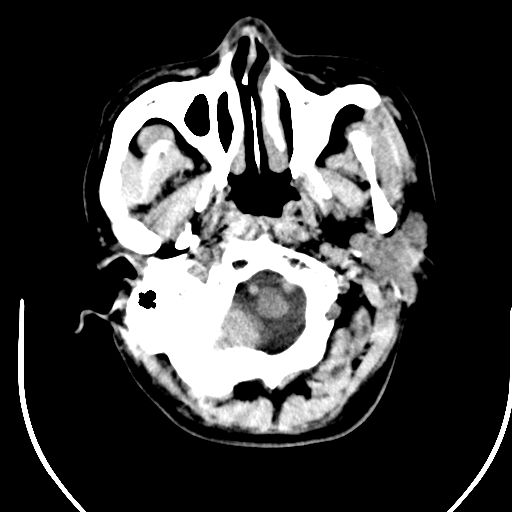

标题: CT25423:头部外伤意外发现右顶叶??? [打印本页]

标题: CT25423:头部外伤意外发现右顶叶???

ct值约13hu。

边缘清晰,没有占位效应,不像脑沟,结合ct值,软化灶可能吧

与脑沟没关系,小软化灶或陈旧性感染吧!

看样年纪不小了直接报腔梗,当然你要想报软化灶也是一样的

考虑右侧额叶巨腔隙灶;建议必要时行mri检查。